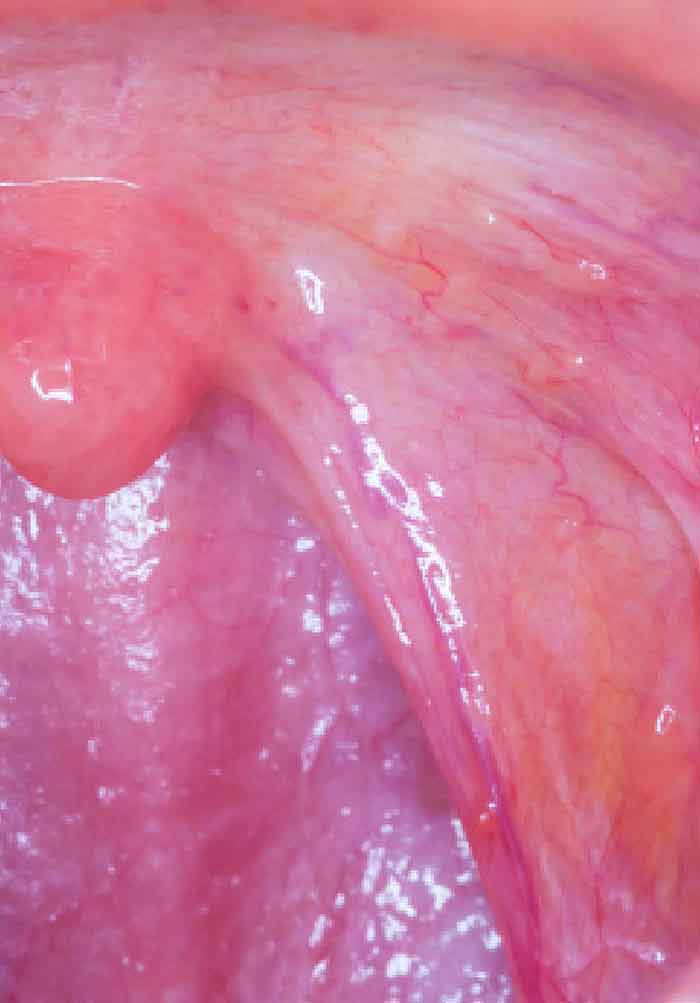

Lesion On The Anterior Floor Of The Mouth With Irregular

Oral Tonsil In The Floor Of Mouth Ectopic Oral Tonsillar